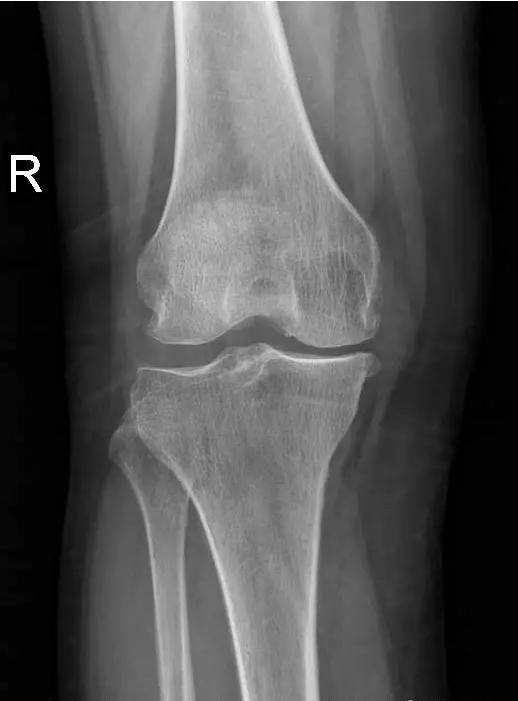

术前片:

术后图如下: